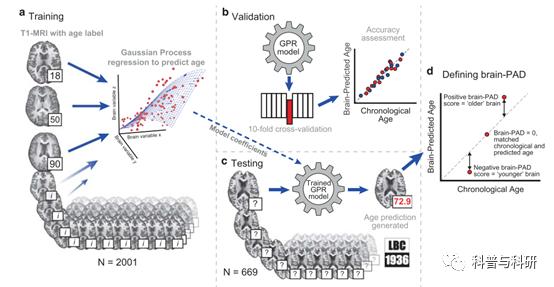

大脑脑龄预测 (理论+代码讲解+实操) |

1.Brain age的基本概念 2.高斯过程回归的概念+代码实操 3.支持向量回归(SVR)概念+代码实操 4.结果可视化及解读 |